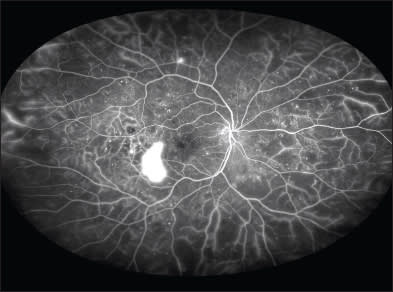

The majority of these diseases, such as diabetic retinopathy, hypertensive retinopathy, central retinal vein occlusion, and ocular ischemic syndrome, may affect the entire retina. Other diseases, however, including sickle cell retinopathy and Coats disease, may only present with changes in the retinal periphery, making imaging more difficult (Figure 1).

Figure 1. A widefield angiogram of a patient with Coats disease, demonstrating peripheral neovascularization and capillary dropout that could potentially be missed with traditional imaging (imaged with the Optos 200 Tx).